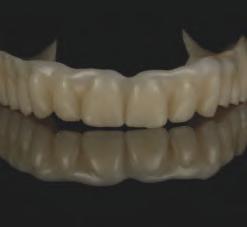

Instrumentele d g tale de astăz pentru stomatolog e pot f ut l zate de la etapa de plan f care până la restaurăr le f nale. După cum demonstrează acest art col, plan f carea tratamentulu poate f real zată în mod d g tal pentru ef c ență ș rezultate îmbunătăț te. Procesul complet al protezelor în cazul prezentat a var at de la ut l zarea punctelor de refer nță sol de ex stente pr n ntermed ul m n - mplantur lor ex stente,

fotograf a b d mens onală (2D), plan f carea d g tală a mplantur lor, scanarea ntraorală, până la o metodă de mpr mare în 3 d mens un (3D) pentru fabr carea unu protot p de reab l tare fullmouth. Această abordare a perm s stab l rea une d mens un vert cale corecte a ocluz e ș a une estet c bune. S-au folos t mater ale progres ve precum z rcon a monol t că ntegrală cu contur total pentru a obț ne estet ca ș un rezultat durab l.

CONCLUZII

Actualmente nstrumentele d gtale în stomatolog e perm t furnzor lor să obț nă rezultate prev zb le în mod ef c ent pentru cazur complexe precum reab l tăr le full-mouth. Ex stă benef c cons derab le în ut l zarea fotograf e d g tale 2D sau a scanăr lor fac ale 3D pentru a crea pac enț v rtual . Acest lucru perm te cl n c en lor ș tehn c en lor să exam neze reperele estet ce ș funcț onale pe măsură ce cazul este procesat, de la d agnost c până la fabr carea restaurăr lor f nale.